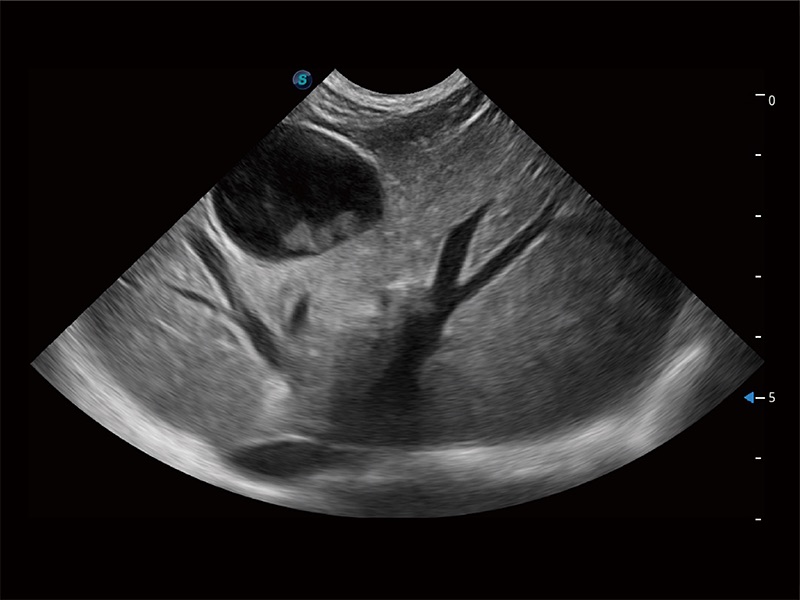

动物是人类最亲密的朋友和最值得信赖的伙伴。乐玩lewin国际也一直致力于探索动物专用的超声影像解决方案。全新推出的ProPet系列,是乐玩lewin国际在动物超声影像智能化、专业化、精准化的一次跨越式革新。动物不能用言语来表述自己的不适,通过超声影像,ProPet系列搭建了动物医生与不同物种沟通的“桥梁”,为动物医生注入了“治愈之力”。 ProPet 80 是乐玩lewin国际匠心打造的一款高端动物专用彩超,采用性能卓越的全新硬件架构,极大提升超声系统的运行效率和数据处理能力,帮助动物医生从容应对日益增多的挑战性病例和日益多样化的临床需求。

高性能和先进的临床应用工具可以为动物医生提供临床信心。ProPet 80 搭载了先进的腹部和浅表应用工具,帮助医生在日常临床实践中发挥前所未有的作用。

ProPet 80 全新的动物超声智能软件和丰富的探头群,为动物医生提供了高清晰度和精细分辨率的图像,无论在宠物、马科、畜牧还是实验室动物等应用中都可以轻松应对,为您的日常工作带来满意的体验。